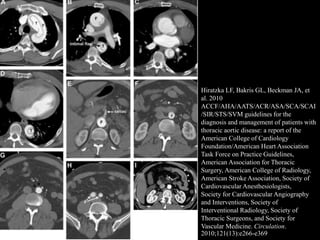

Computed Tomography

• Key: intimal flap separating 2 lumens

• Spiral fashion: FL from Rt anterolateral wall of

ascending aorta extend to Lt posterolateral

wall of descending aorta

• ECG-gated 64-detector CT

– Triple rule out: evaluate patient with chest pain

with potential causes: AD, PE, ACS

– Pulsation artifact: most common cause of misdx

Hiratzka LF, Bakris GL, Beckman JA, et

al. 2010

ACCF/AHA/AATS/ACR/ASA/SCA/SCAI

/SIR/STS/SVM guidelines for the

diagnosis and management of patients with

thoracic aortic disease: a report of the

American College of Cardiology

Foundation/American Heart Association

Task Force on Practice Guidelines,

American Association for Thoracic

Surgery, American College of Radiology,

American Stroke Association, Society of

Cardiovascular Anesthesiologists,

Society for Cardiovascular Angiography

and Interventions, Society of

Interventional Radiology, Society of

Thoracic Surgeons, and Society for

Vascular Medicine. Circulation.

2010;121(13):e266-e369